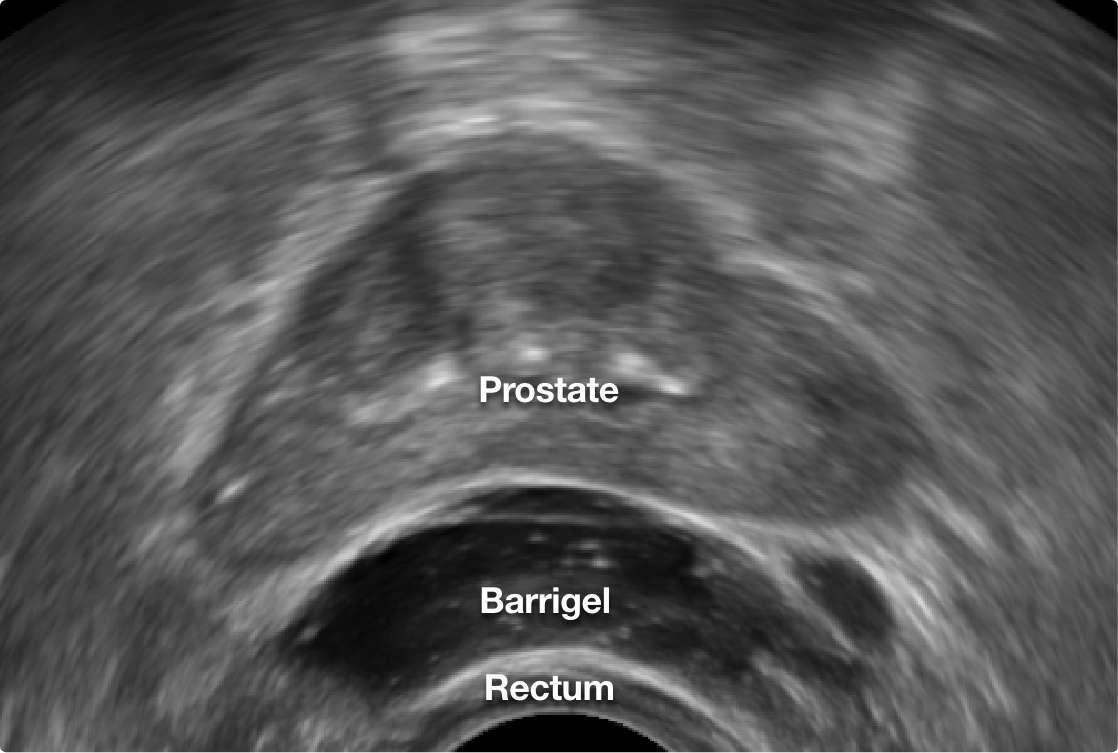

Barrigel can be viewed clearly on transrectal ultrasound (TRUS), the imaging machine used to guide your doctor’s placement during the procedure. This real-time visibility provides your doctor control and precision over the shape and placement of the spacer.1

TRUS image courtesy of Dr. Neil F. Mariados, Radiation Oncologist; New York, United States